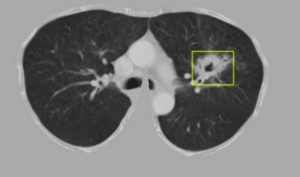

Nhóm nghiên cứu tại Đại học Khoa học và Công nghệ Hà Nội thiết kế hệ thống AI đọc kết quả phim chụp chỉ 5-10 giây, trong khi bác sĩ cần 5-10 phút.